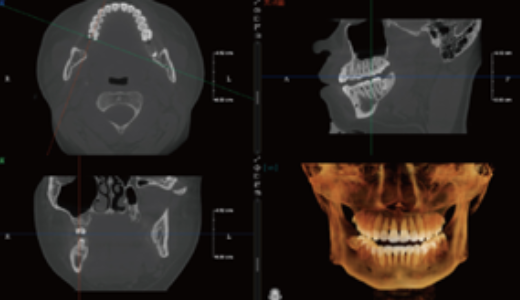

Tecnologia Inovadora Root-Bone Glass

Suporta o posicionamento manual dos dentes, a remoção dentária e a observação tridimensional da câmara pulpar.

Permite o planeamento imediato de extrações e implantes.

Planeamento Virtual de Implantes

Permite a simulação de procedimentos de implantes (implante + pilar + coroa), ajudando a selecionar o implante mais adequado.

Fornece alertas de proximidade ao canal nervoso, aumentando a segurança cirúrgica.

Facilita a comunicação entre médico e paciente, permitindo ao paciente visualizar claramente o procedimento de implante planeado.